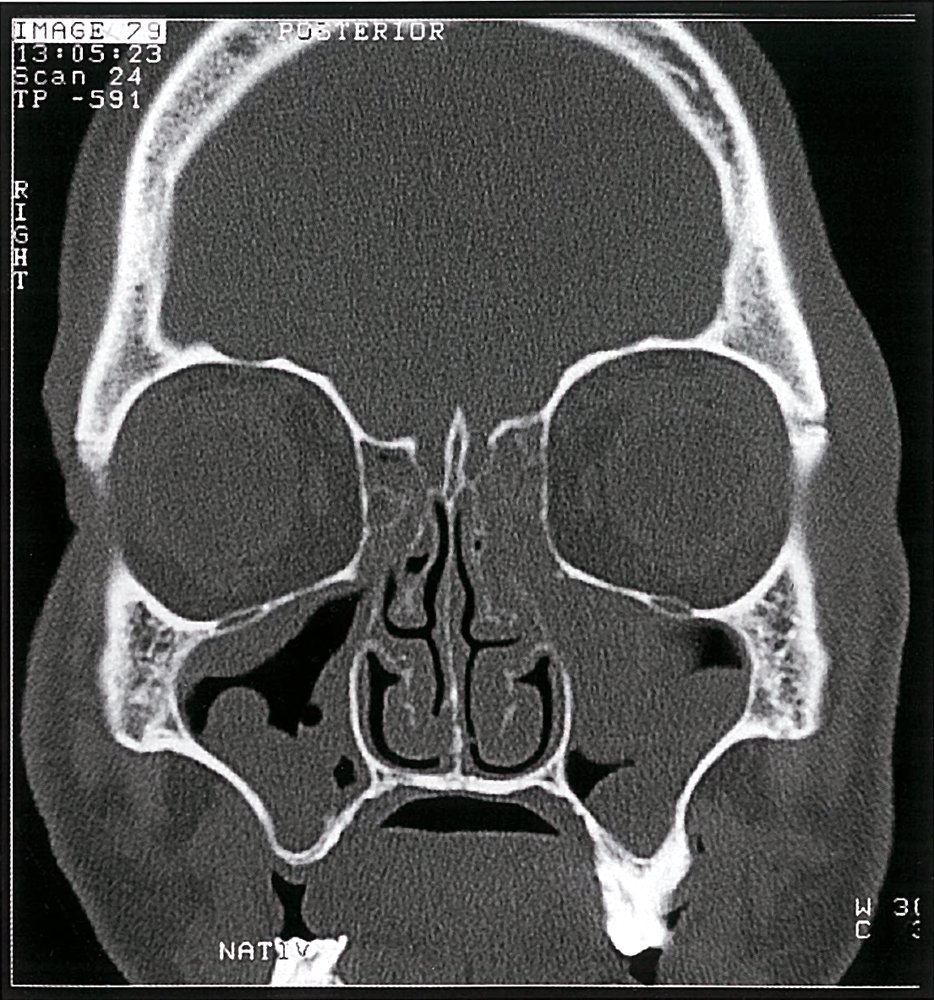

부비동염

비강기관내 삽관(nasotracheal intubation) 및 비강 튜브와 더불어 부비동염의 위험인자로 두부외상, 스테로이드 사용력, 기왕의 항생제 치료 등이 있다.

비강 튜브는 부비동의 점액 누적과 부비동염의 발생을 초래하는 상악동공 폐색의 단점이 있다. 16명의 환자에 대한 전향적 연구에서 비강기관내삽관 시행 후 8일 차에 CT 이미지 촬영을 한 결과 환자의 87%가 상악동과 접형동에 각각 감염이 발생하였고, 점액누적, 혼탁화, 점막비후 등 사골부비동(50%), 전두동(12.5%) 감염 순이었다. 또한 일부 연구에서는 장기 비강기관 내 삽관으로 인해 2차적으로 발생한 부비동염을 패혈증의 원인으로 지목하였다. Holzapfel 등은 비강 기관 내 삽관이 인공호흡기 관련 폐렴과 2개월 사망룰 증가와 상당한 연관이 있다는 점을 밝혔다. 이러한 자료를 토대로 현재 대부분의 의사가 선호하는 삽관의 경로는 경구기관(orotracheal)이다.